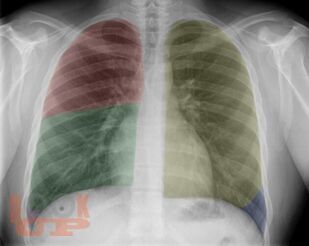

В учебном пособии представлена информация о нормальной рентгеновской анатомии органов грудной полости, вариантной анатомии, наиболее частых аномалиях развития, скиалогии, алгоритме описания рентгенограмм и основных требованиях по оформлению протокола рентгенологического исследования.